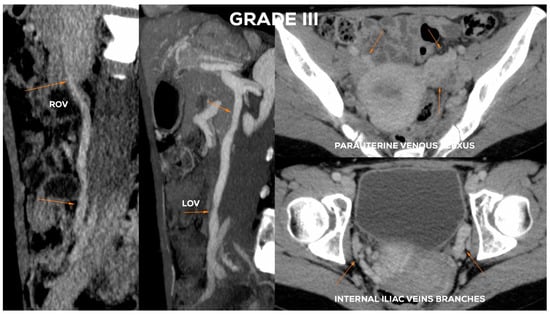

4.2.5. Grade III (GIII)

| GIII | >8 | (++) | 7–8 | <7.5 | <7.5 | (+/++) | <7 | <6.5 |